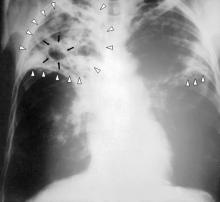

Negli studi clinici, a quattro anni dalla somministrazione, il 94% dei pazienti trattati con etranacogene dezaparvovec aveva interrotto la profilassi tradizionale e manteneva livelli di attività del Fattore IX vicini alla norma, con una riduzione significativa dei sanguinamenti